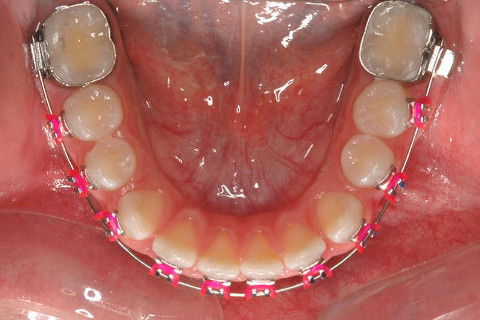

INSTALAÇÃO APARELHO FIXO SUPERIOR E INFERIRO (ROTH)

CLASSE I

CLASSE II